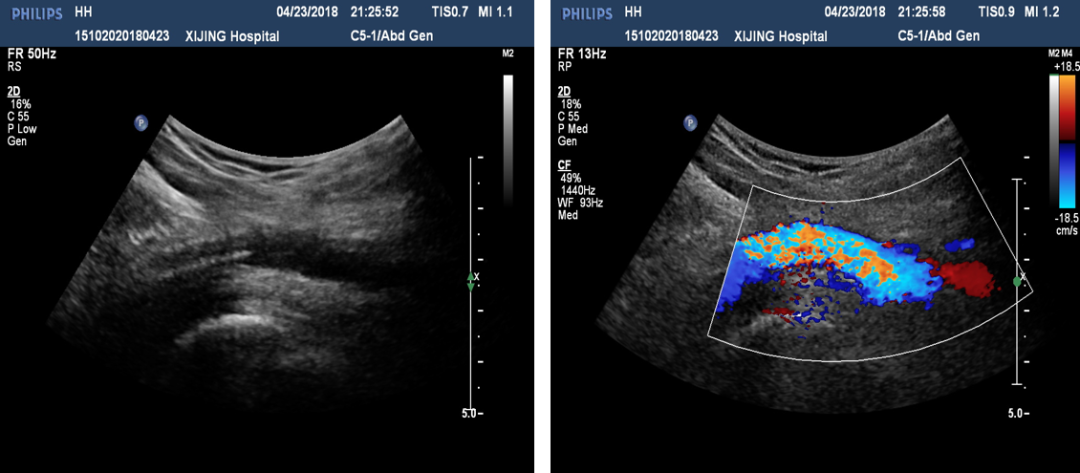

术前超声评估:提示腘动脉血栓。

图:胫腓干血栓及直径

胫后及腓动脉起始处彩色血流图

手术操作:

图:穿刺成功后导丝位于股浅动脉内

图:顺导丝置入Rotarex血栓抽吸装置

图:头端经过后超声图像

图:抽吸之后效果

图:瞬时监测

图:超声引导下导丝开通胫后动脉

图:球扩后胫后动脉

图:术前胫后动脉